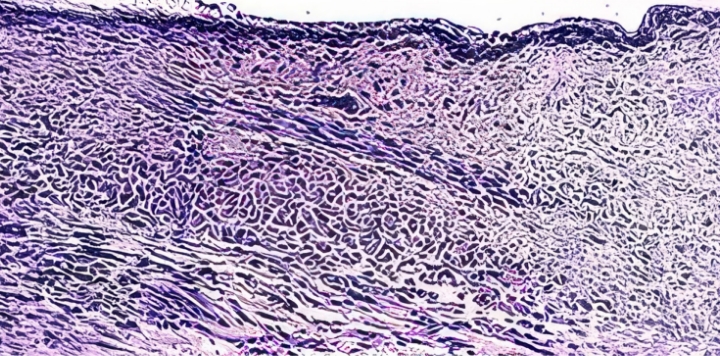

질 조직 정상 수준으로

회복되며 질 건조증 개선

JS트로겐 투여 시, 각화세포층을 포함한

질 조직이 정상에 가깝게 회복